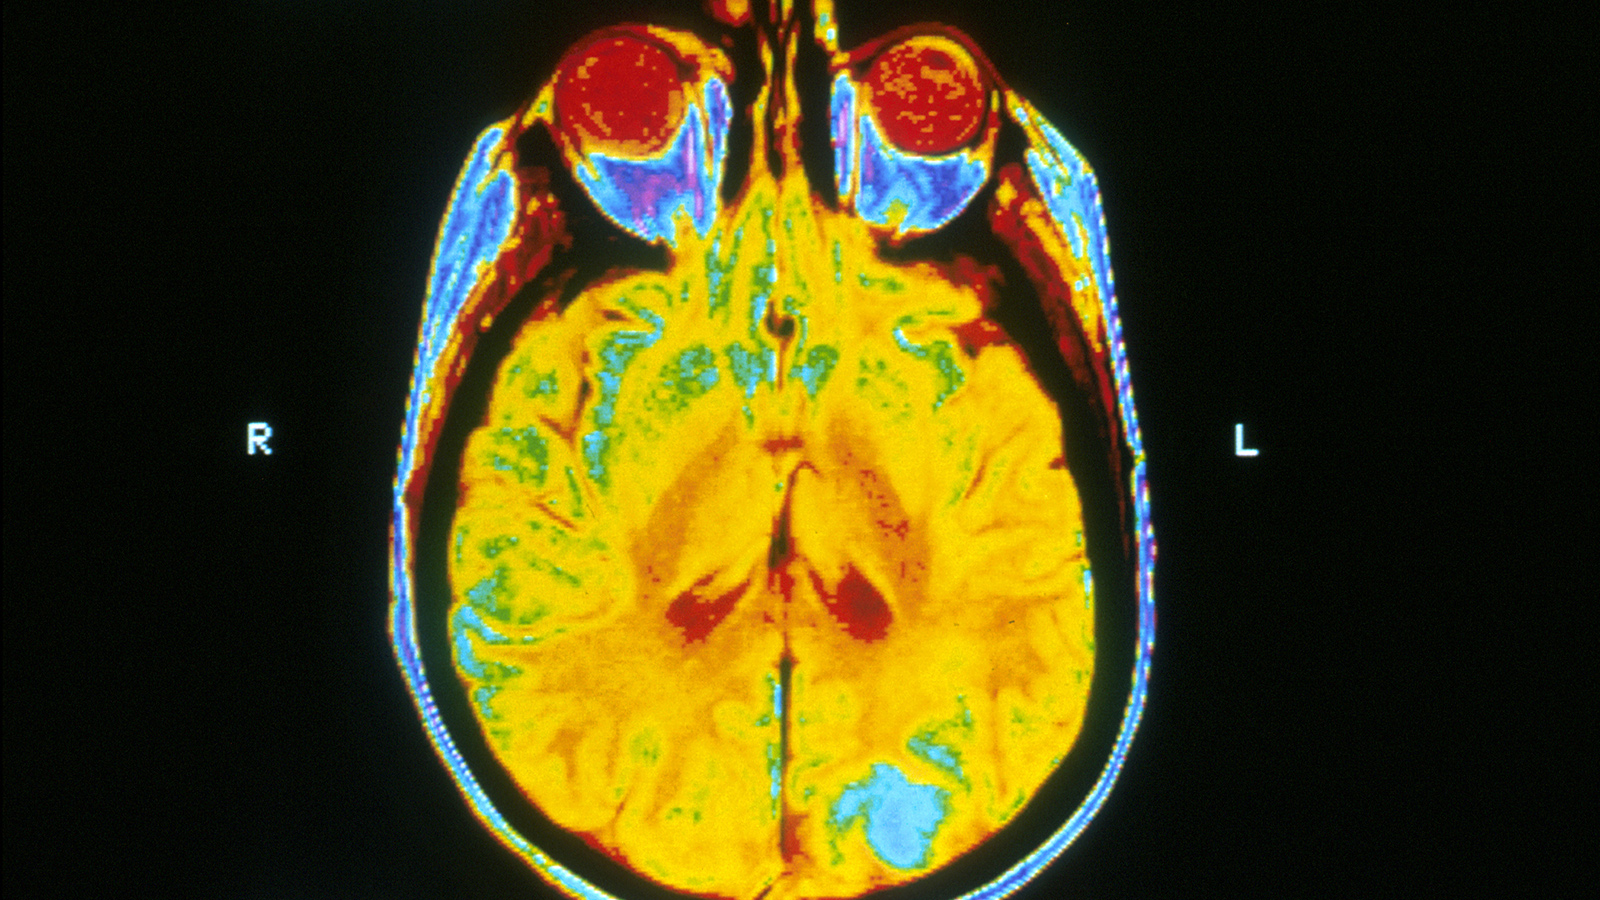

Epilepsy surgery has a success rate of only 50%. This digital brain may change that.

Using patient data and AI, French researchers have created a digital model of the brain to figure out which brain region needs removed.